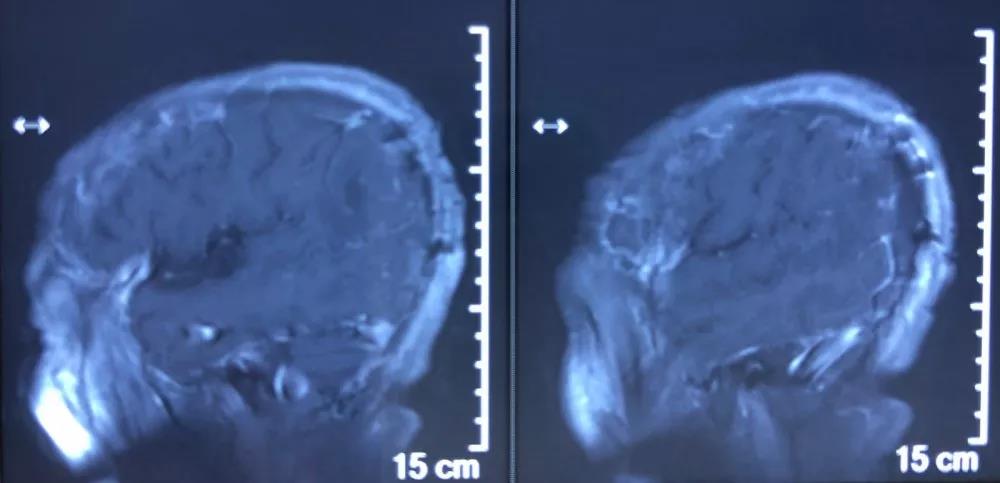

入院后给予Ⅰ级护理,消肿止痛等对症治疗,行术前准备,择期手术治疗。患者于1月23日在全身麻醉下行右顶枕部开颅脑膜瘤切除术,肿瘤大小约3×2×2.5cm。患者术后恢复良好,无任何神经功能障碍,复查颅脑MRI增强扫描提示肿瘤全切。